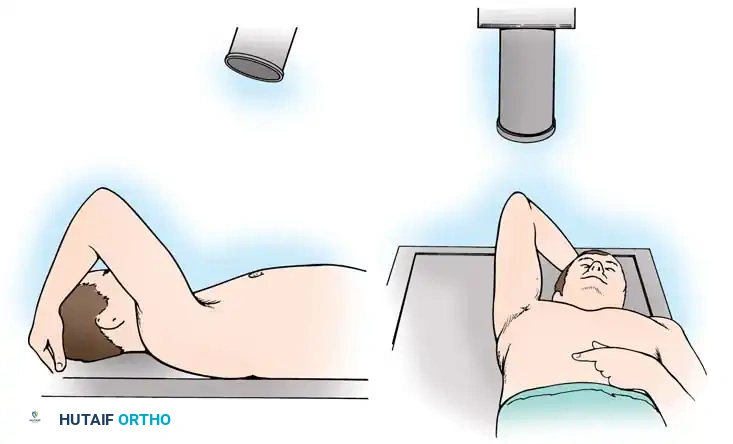

Patient Positioning and Anesthesia

The procedure is typically performed under general anesthesia supplemented with an interscalene regional nerve block for postoperative analgesia. The patient is placed in the beach-chair position with the head secured and the operative arm draped free to allow full manipulation. A mechanical arm holder is highly recommended to control rotation and abduction during the capsular shift.